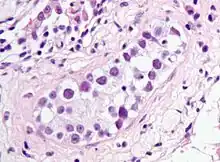

| Intratubular germ cell neoplasia. H&E stain. | |

GCNIS is not palpable, and not visible on macroscopic examination of testicular tissue. Microscopic examination of affected testicular tissue most commonly shows germ cells with enlarged hyperchromatic nuclei with prominent nucleoli and clear cytoplasm. These cells are typically arranged along the basement membrane of the tubule, and mitotic figures are frequently seen. The sertoli cells are pushed toward the lumen by the neoplastic germ cells, and spermatogenesis is almost always absent in the affected tubules. Pagetoid spread of GCNIS into the rete testis is common. Immunostaining with placental alkaline phosphatase (PLAP) highlights GCNIS cell membranes in 95 percent of cases. OCT3/4 is a sensitive and specific nuclear stain of GCNIS.[3]

ITGCN. H&E stain.